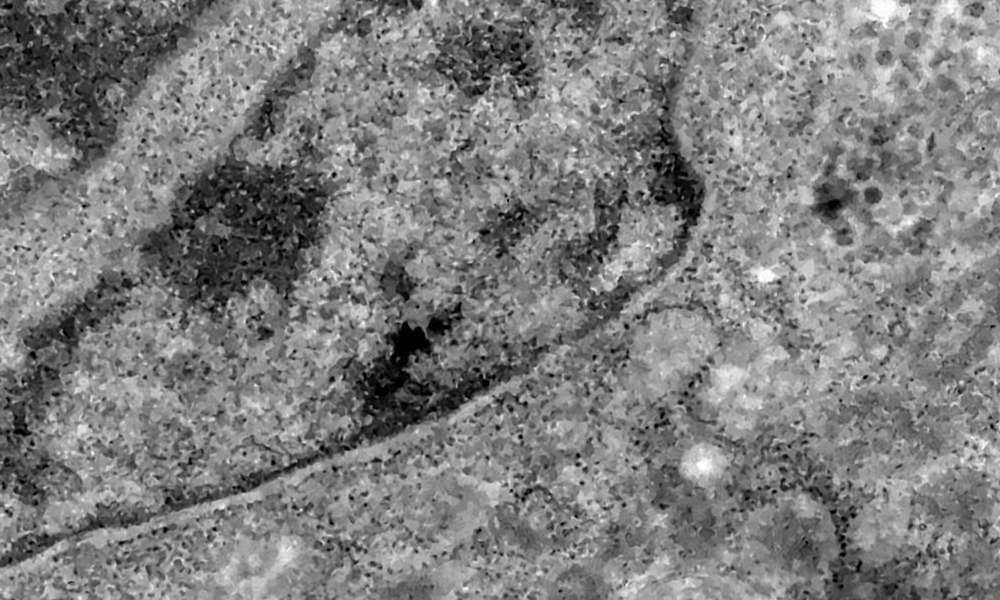

Foto: Reprodução / Fonte: Agência Brasil

Pesquisadores brasileiros conseguiram, pela primeira vez, detectar a presença do coronavírus em retinas. O estudo pode contribuir para compreender melhor a dinâmica do vírus e as sequelas em pacientes infectados.

Os pesquisadores analisaram retinas de pacientes que morreram em decorrência da covid-19 e compararam com fotos dos olhos desses pacientes quando vivos para analisar as diferenças e formas de aferir a presença do vírus a partir da retina.